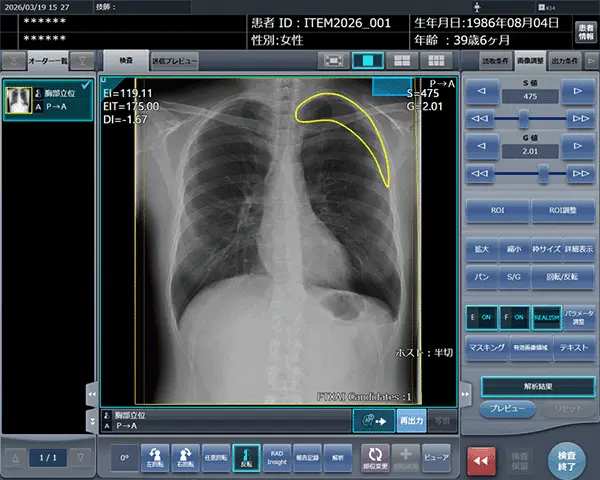

コンピューターのスクリーンショット

「CXR Finding-i 気胸検出タイプ」により解析された気胸の検出領域を表示